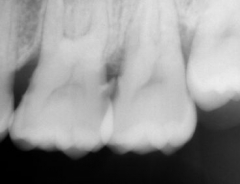

検査1)レントゲン撮影 歯を支えている骨がどのくらい残っているかレントゲンで確認します。

検査3)実際に骨がどのくらい吸収されているかを測定します。